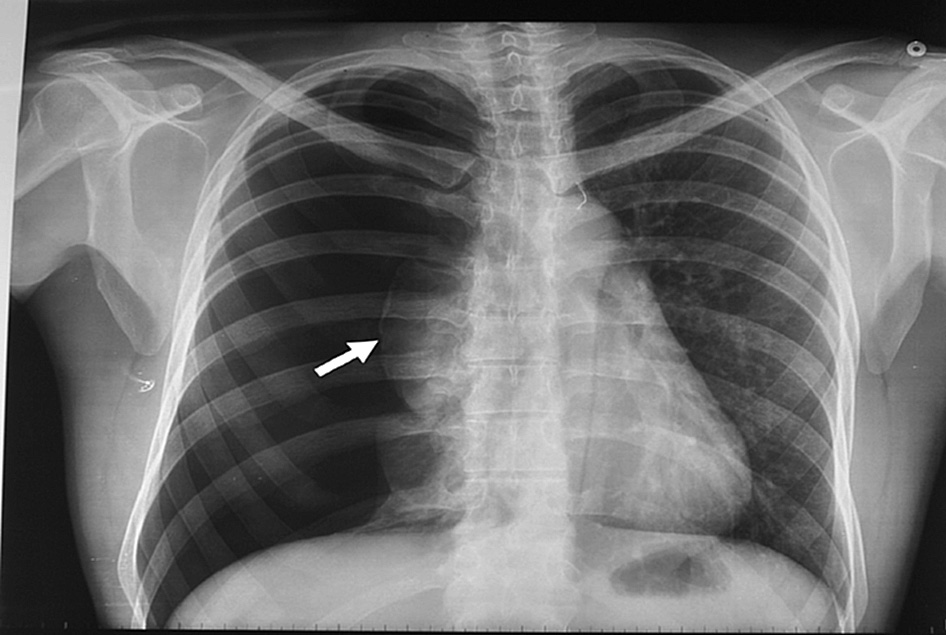

Manejo conservador del neumotórax espontáneo moderado a grande

En un ensayo clínico que comparó la intervención inicial vs manejo conservador se encontró resolución del neumotórax a las 8 semanas en 98,5% vs 94,1% de los pacientes, respectivamente. New England Journal of Medicine, 30 de enero de 2020

Neumotórax espontáneo: aspiración con aguja vs drenaje con tubo

El tratamiento inicial de aspiración con aguja obtiene mejore resultados inmediatos y acorta los tiempos de internación. European Respiratory Journal, abril de 2017